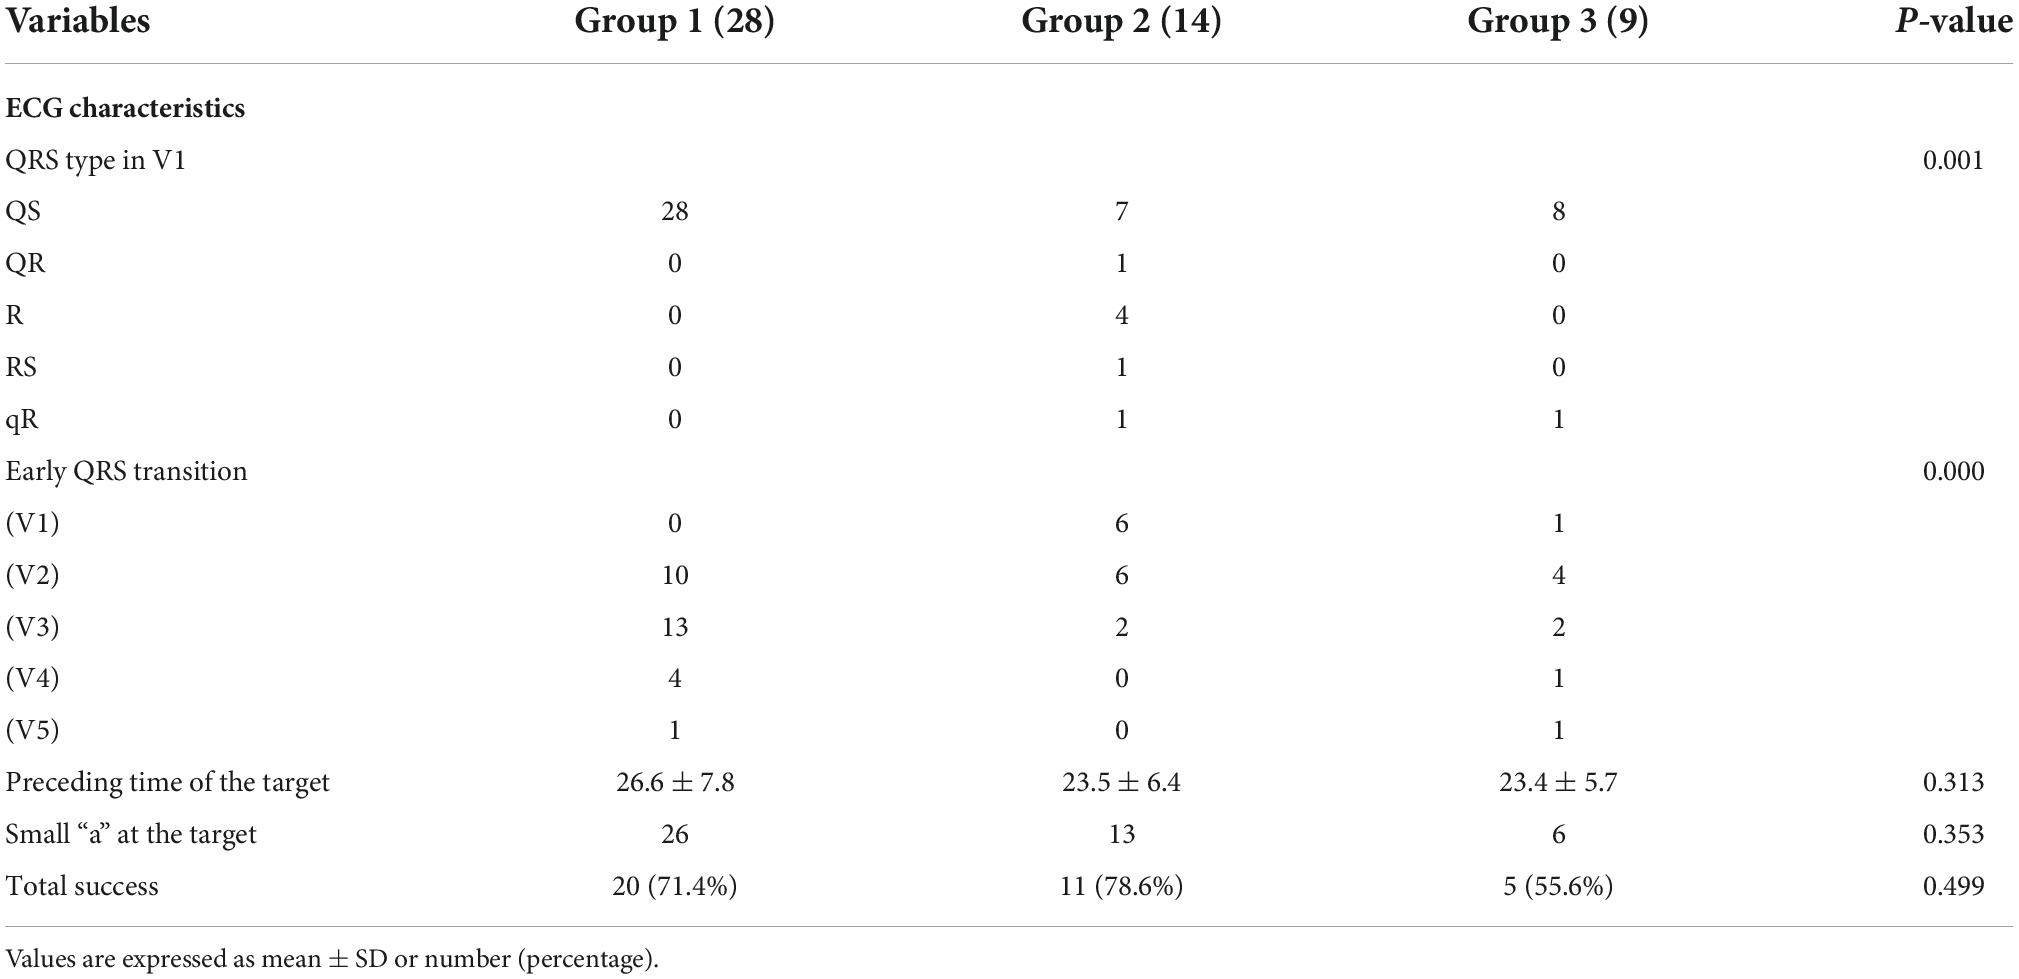

As a result, tall R or RR’ pattern waves were all found in leads I and aVL. In all but 5 patients, the surface ECG demonstrated an initial q or QS wave at lead V1, and the other 5 patients demonstrated an R or Rs pattern. There was a significant difference between Group 1, Group 2 and Group 3 in terms of the morphological features in the precordial lead (Table 2) (p = 0.001). The V1 lead showed a positive wave (qR type) in only one patient in Group 3, while in Group 2, a positive wave was found in 7/16 patients (QR, R, RS, or qR type). At the V1 lead, a QS type was found in 34/35 patients in Group 1, while it was found in 9/14 patients in Group 2 and 8/9 patients in Group 3 (p = 0.001). In Group 1, the precordial R wave transition occurred at or beyond V3 in 18 patients (64.3%); however, 2 patients in Group 2 exhibited the precordial R wave transition at or beyond V3 (14.3%), and 4 patients in Group 3 (p < 0.001).

Table 2. Comparisons of ECG and electrophysiological characteristics of VAs in basal septum between the right side (Group 1), left side (Group 2) and intramural foci (Group 3).